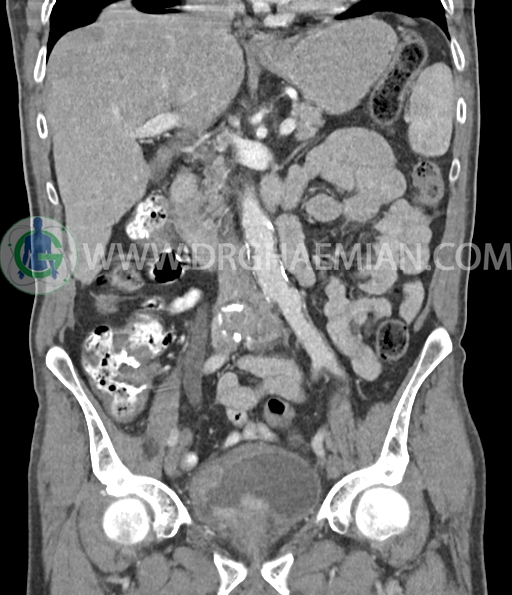

سی تی اسکن لگن و شکم از تشعشعات برای ایجاد تصاویر عرضی مقطعی از لگن و شکم استفاده می کند. در این کیس سرطان سلول انتقالی کلیه، ضایعه کبدی، دیورتیوکولوز، کیست کورتیکال در کلیه چپ، پروستات بزرگ شده، افزایش ضخامت دیواره مثانه دیده می شود.

در سی تی اسکن اسپیرال شکم و لگن با و بدون کنتراست خوراکی و وریدی (مولتی دیدکتور 16 با مقاطع ظریف و بازسازی های ساژیتال و کرونال) :

ضایعه ای در کیسه صفرا، مجاری صفراوی، طحال، کلیه چپ ، پانکراس و آدرنالها مشهود نیست مایع آزاد در حفره شکم و لگن رویت نمی شود.

کلسیفیکاسیون دیواره ائورت مشهود است.

افزایش ضخامت جداری و نامنظمی و لوبولاسیون همراه باenhancement مطرح کننده انفیلتراسیون و ضایعات تومورال در سمت راست ناحیه ترایگون و دیواره لترال راست مثانه دیده می شود که باعث اتساع حالب راست و هیدرونفروز moderate در کلیه راست شده است . این یافته های می توانند مطرح کننده TCC باشند .fat stranding در اطراف مثانه مشهود است. بیرون زدگی توده مانند به قطر 18mm در سمت راست ناحیه ترایگون دیده می شود که می تواند مطرح کننده گسترش اکسترا وزیکولر تومور باشد . لنفادنوپاتی با SAD=10mm درlevel ایلیاک داخلی چپ رویت شد . لنف نود دیگر با SAD= 5mm در همین ناحیه مشهود است. با توجه به این یافته ها stage احتمالی تومور T3، N1 or N2 می باشد .